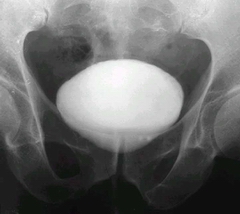

老人較容易得膀胱結(jié)石的原因? 膀胱結(jié)石患者比較多,對(duì)于膀胱結(jié)石的病因,老年人了解的很少,研究表明,老年人得膀胱結(jié)石的幾率更大,是什么原因?qū)е铝诉@種情況呢?齊齊哈爾?現(xiàn)代醫(yī)院專(zhuān)家為大家介紹。

齊齊哈爾?現(xiàn)代醫(yī)院專(zhuān)家指出,膀胱結(jié)石患者患上膀胱結(jié)石的原因是很多的a、可能是由上泌尿道結(jié)石掉下來(lái)的,最后形成膀胱結(jié)石。

c、可能是原發(fā)性的結(jié)石。